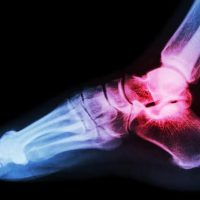

Прилагайки една от най-ефективните терапии за лечение на сухожилия и лигаменти, благодарение на огромния опит и екпертиза на доктор Кавалино ние сме способни да помагаме на хора из цяла България да спрат да чувстват болка.